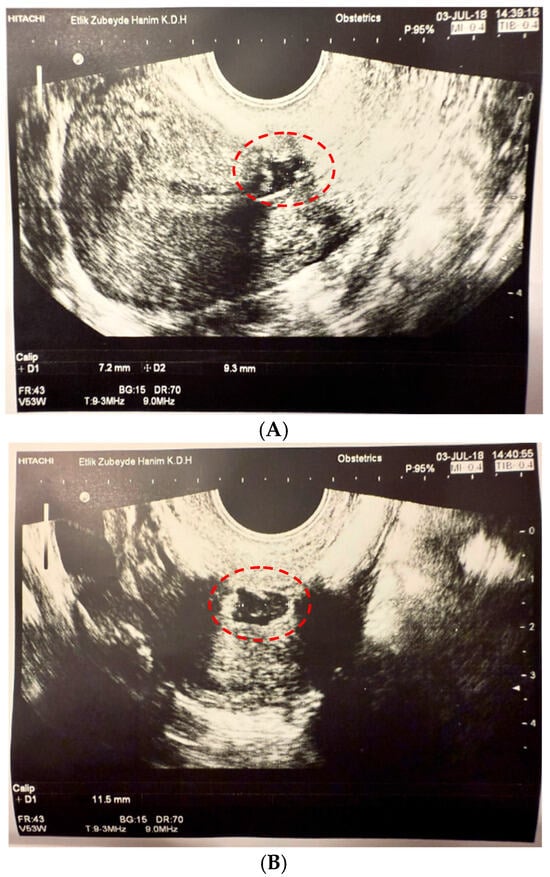

In our study, a new classification system based on isthmocele volume was developed, differing from existing classifications in the literature, such as Gubbini’s classification [19]. Since the isthmocele generally has an approximately triangular pyramid shape, its volume was calculated using the formula: Volume = (Height × Width × Depth)/3 (Figure 1). Based on the obtained volume values, patients were categorized into two groups. Defects with a volume of 50 mm3 or less were classified as Grade 1, while those exceeding 50 mm3 were designated as Grade 2. This novel volume-based Er-Kay Classification has facilitated a more comprehensive assessment of cesarean scar defects and enabled a more precise analysis of their correlation with clinical symptoms.

Figure 1. Calculation of Isthmocele Volume in Ultrasonography ((A) Height-Depth Measurement (D1*D2), (B) Width Measurement (D1)). Height-Depth Measurement is indicated as D1*D2 in panel (A), and Width Measurement is indicated as D1 in panel (B) (as described in the figure legend). The measured areas are highlighted with red circles on the images.